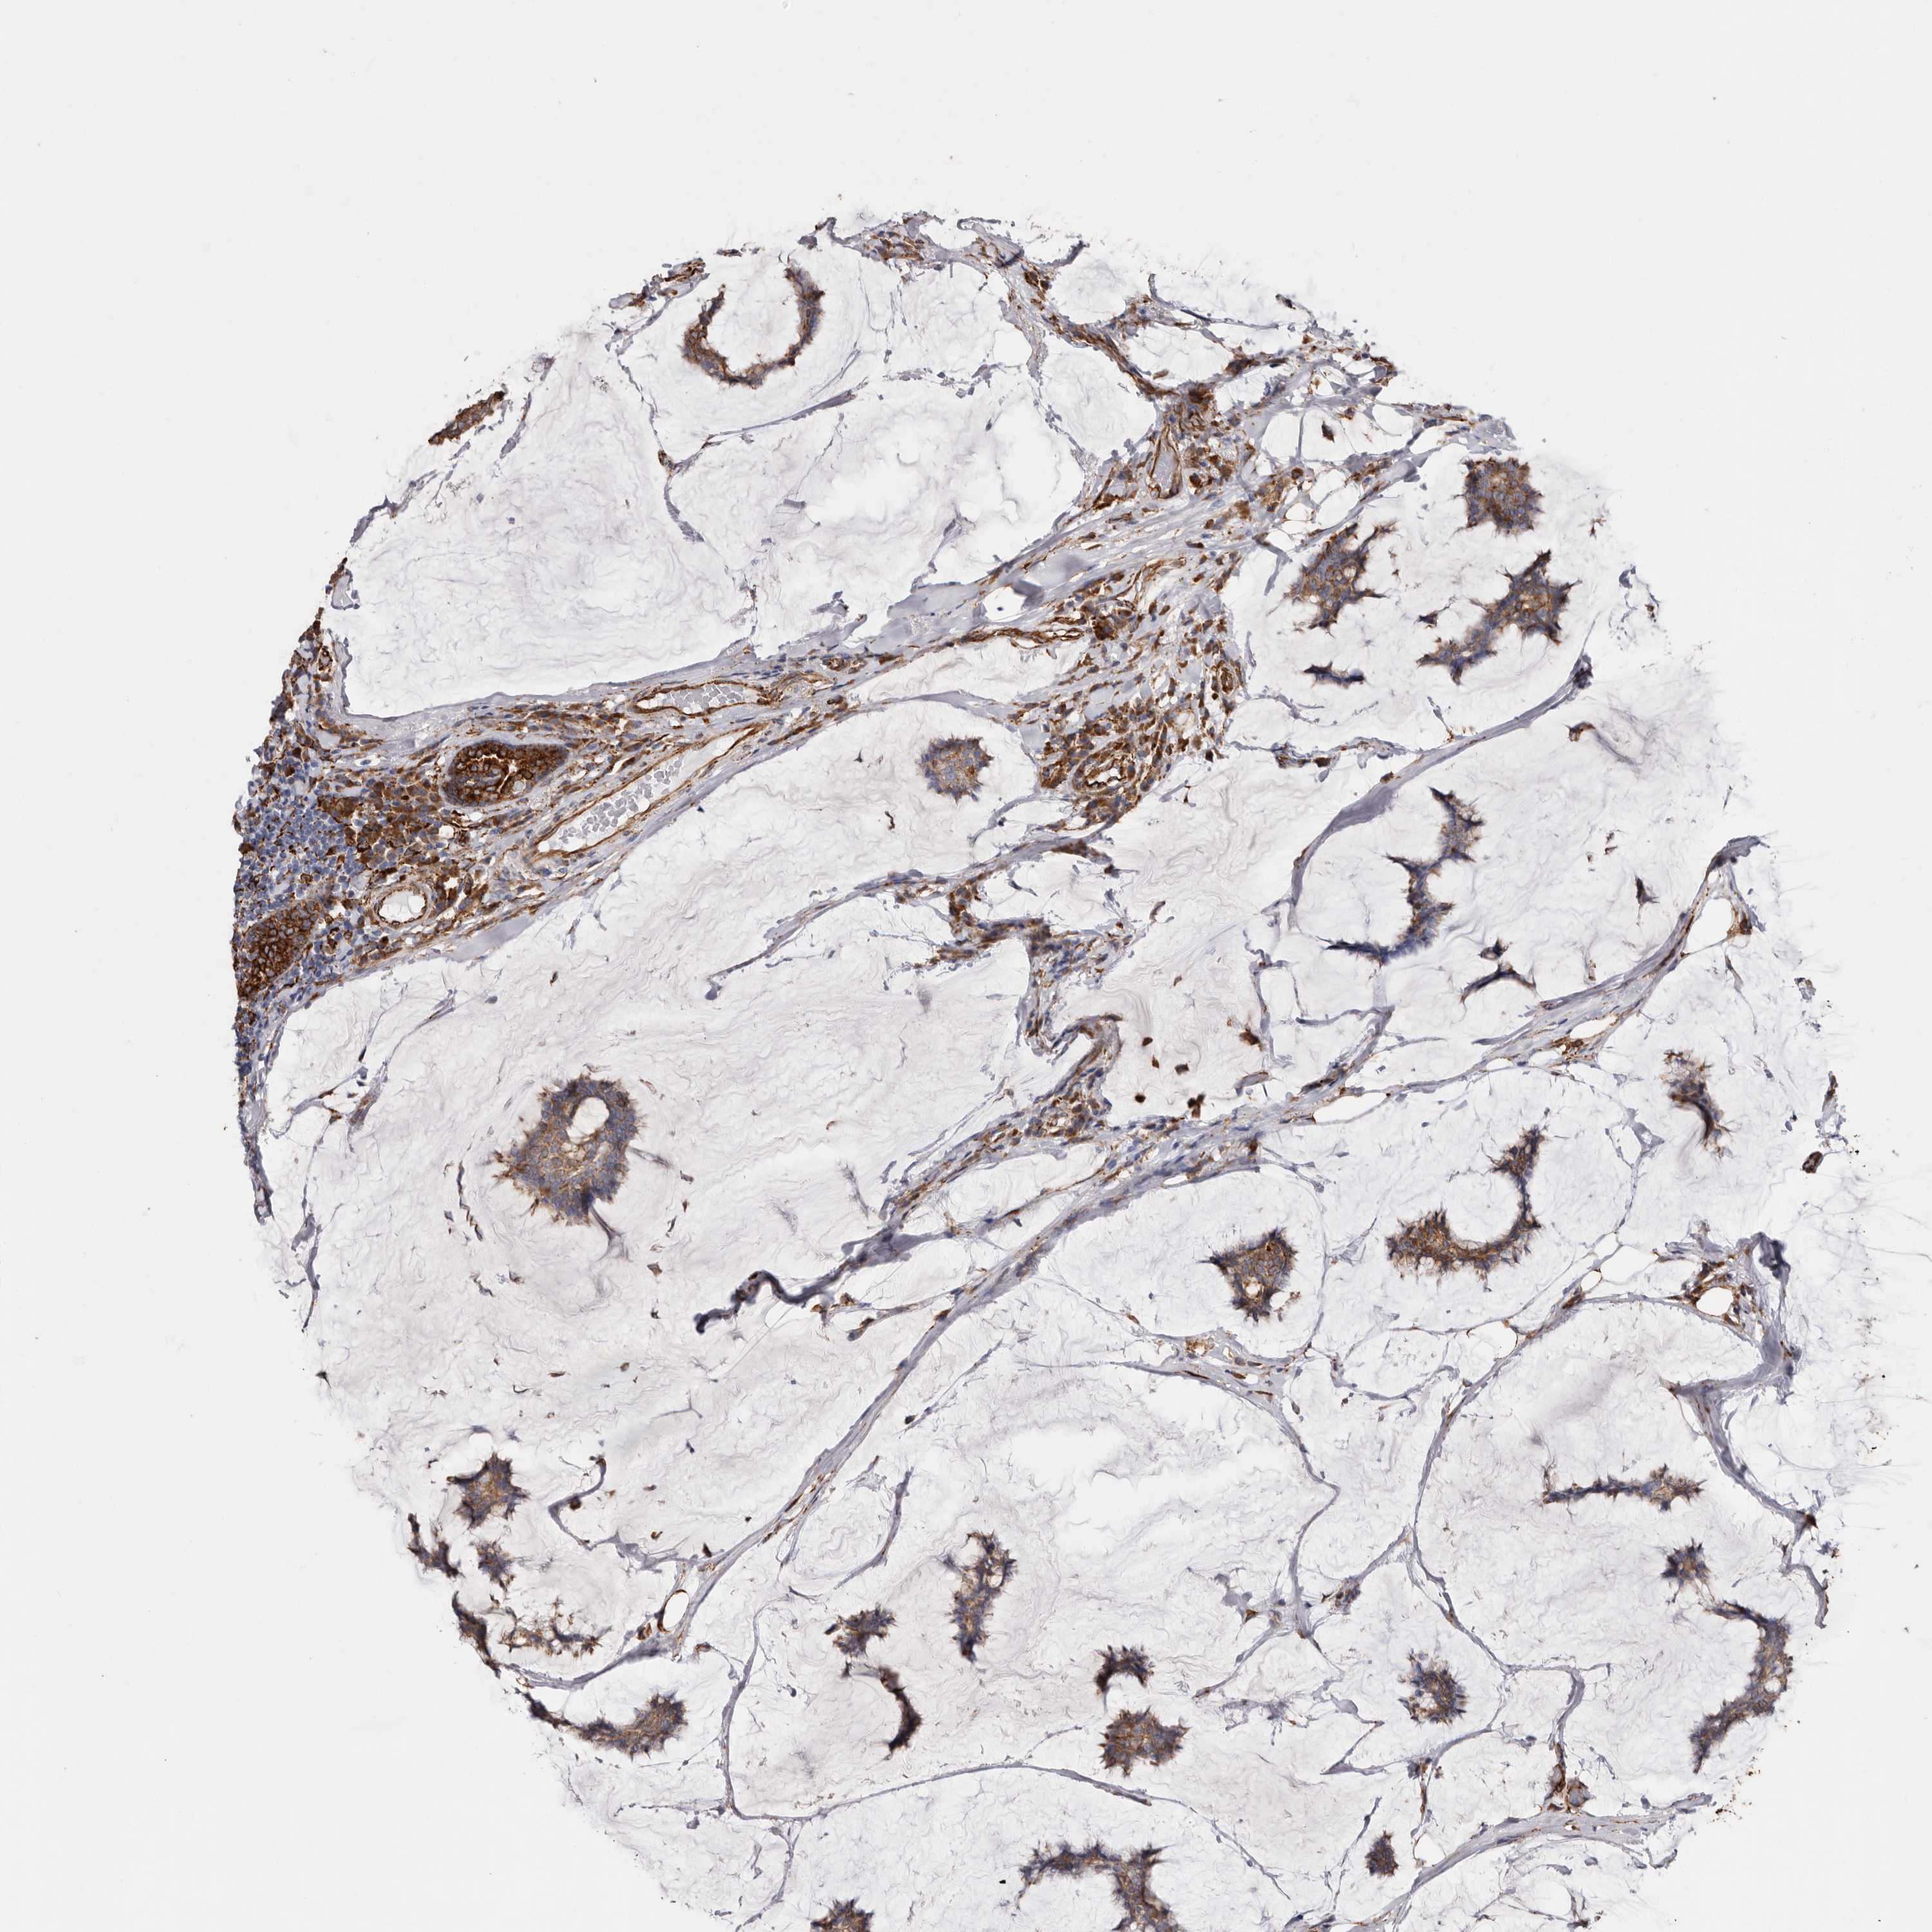

CANCER BREAST CANCER Show tissue menu

BRCA TCGA BRCA VALIDATION PROTEIN EXPRESSION